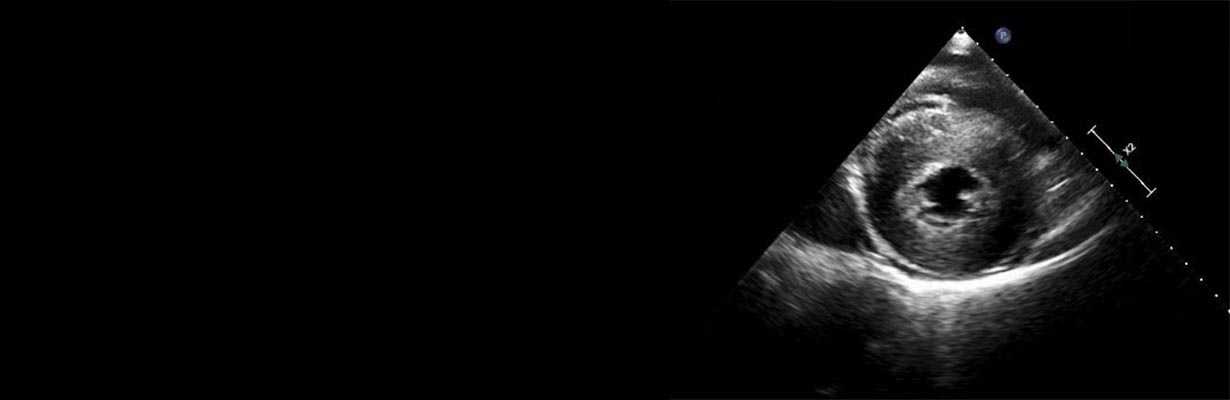

In this video, Dr. R. R Kasliwal, Chairman - Clinical & Preventive Cardiology, Medanta – The Medicity, will discuss the importance of LVH on echocardiography. When LVH is seen in patients with hypertension, then it signifies that the blood pressure is not completely under control. If the blood pressure is not controlled then he might suffer from disease of arteries of the heart also. LVH and LV mass are two the parameters which are important. In an LVH patients, medicines also differ. If he has LVH then different set of medicines are given. If he doesn’t have LVH, then different medications are given in hypertensive patients.